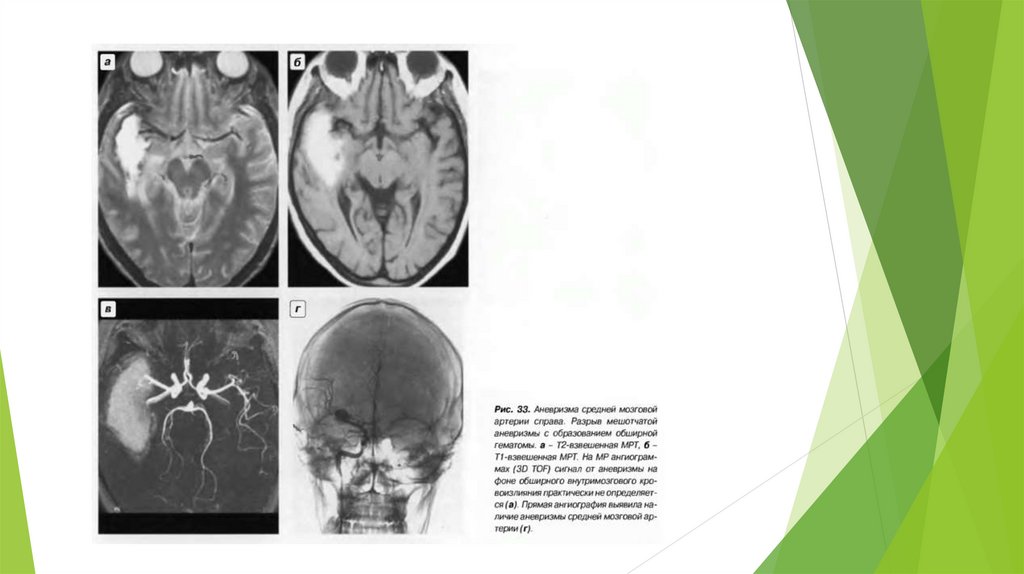

3 На средней мозговой артерии (СМА) - 19%.